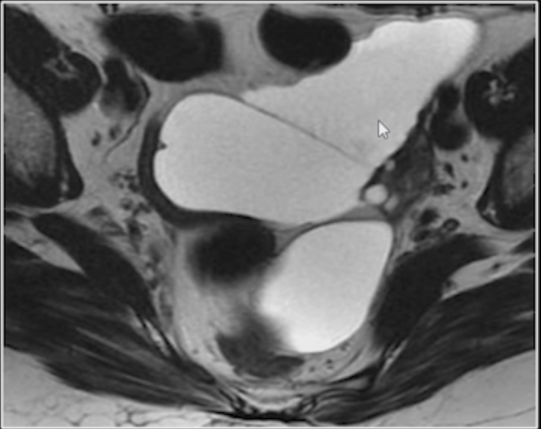

Leiomioma exofítico.